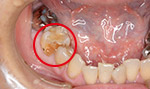

症例4(むし歯→白く)

30代の患者さんで以前銀歯が入っていて気になっていたので白くしたいと希望した方です。

自然な感じに白くなって良かったと喜んでおられました。

回数2回 20000円

術前

術後